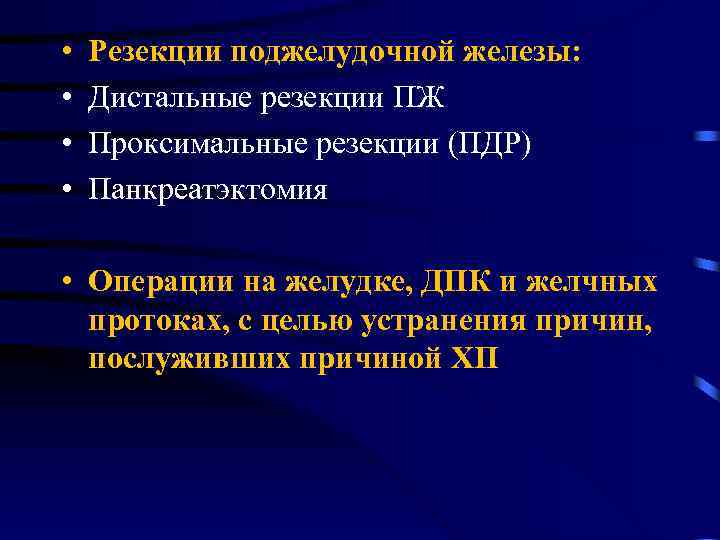

• • Резекции поджелудочной железы: Дистальные резекции ПЖ Проксимальные резекции (ПДР) Панкреатэктомия • Операции на желудке, ДПК и желчных протоках, с целью устранения причин, послуживших причиной ХП